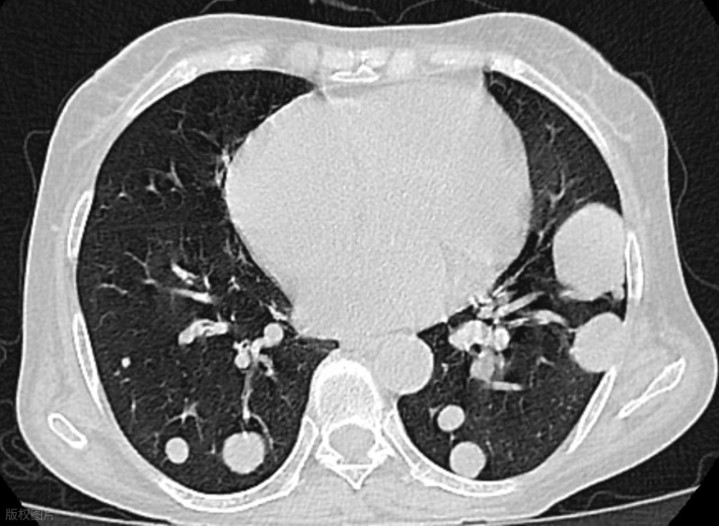

适合那种胸口闷、干咳不断、咳却咳不出痰的朋友。很多人 CT 上提示“结节密度偏高”,但生活中又总感觉胸口像堵着一块石头,说话时间长一点就咽干口干、气不够用。就可以参考这组搭配,川贝能化痰软坚,把硬结的块儿慢慢化开,而桔梗能宣肺、把深层的痰往外带出去。一个化,一个宣,让肺气的出口重新打开。

有很多患者朋友,痰多、胸闷,尤其感觉咽喉有黏腻感、早晨痰多,胸口沉重、易疲倦,伸舌头一看,舌苔白厚,这多半是湿痰壅肺。款冬花与桔梗的组合在这里就非常适合。款冬花能清肺止咳,把“湿痰的火”降下来;川贝母能把痰气带出去,让堵在中间的东西有一个出口。很多人说喝了之后胸口逐渐轻松、咳得更顺,连 CT 上提示的炎症也比之前淡了些。